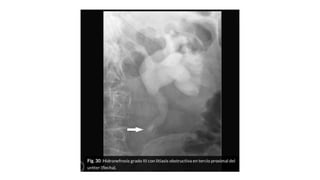

Hidronefrosis

• Dilatación de la vía urinaria

causada por aumento de la

presión de retorno al

obstruirse el flujo por una

causa obstructiva mecánica o

funcional, de origen intrínseco

o extrínseco

• Grado I - Pelvis renal ligeramente dilatada

sin ectasia calicial.

• Grado II - Moderada dilatación pélvica y

calicial (cálices con morfología distal

concava o aplanada).

• Grado III - Gran dilatación pélvica y calicial

(cálices con inversión de su superficie distal

que se muestra convexa) y parénquima

renal normal.

• Grado IV - Pelvis renal muy grande con

cálices muy dilatados y adelgazamiento del

parénquima renal.